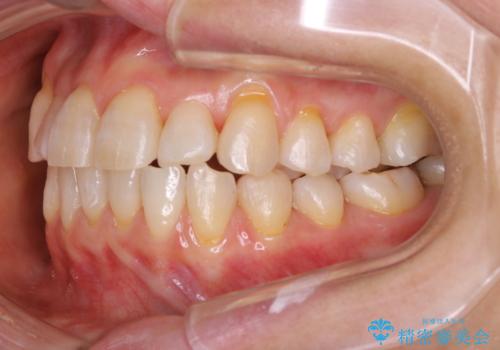

前歯の反対咬合、奥に引っ込んでしまっている歯をインビザラインで治療する

- インビザラインでの治療を希望した患者様です。

上の前歯の反対咬合があり、治療の途中で下の前歯を乗り越える必要があります。

インビザラインでこのような症例を行う場合、乗り越えるのに必要な期間が長くなります。

その為、奥歯で咬みにくい期間が長くなってしまいやすいです。